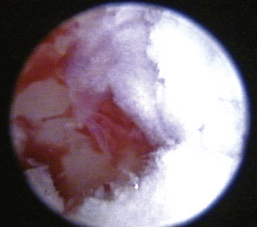

The middle ear consists of an air-filled tympanic cavity, three auditory ossicles, and the tympanic membrane. The tympanic membrane is located at a 45-degree angle in relation to the central axis of the horizontal part of the external ear canal. The tympanic membrane is a semitransparent membrane that separates the external ear canal from the middle ear, is thin in the center and thicker at the periphery, and is divided into two sections, the small upper pars flaccida and the larger lower pars tensa (Figure 20-2). The pars flaccida is the pink, small, loosely attached region forming the upper quadrant of the tympanic membrane that contains small blood vessels. The pars flaccida is usually flat; however, even in the healthy ear one may identify a bulging pars flaccida (Figure 20-3). The exception is the Cavalier King Charles Spaniel, in which a bulging pars flaccida may be indicative of a disease known as primary secretory otitis media (PSOM) (Figure 20-4).

image

Figure 20-3 Bulging pars flaccida in a dog without any external or middle ear disease. 1, Pars flaccida; C, caudal; D, dorsal; R, rostral; V, ventral.

(Courtesy of Dr. Lynette Cole, The Ohio State University, Columbus, Ohio.)